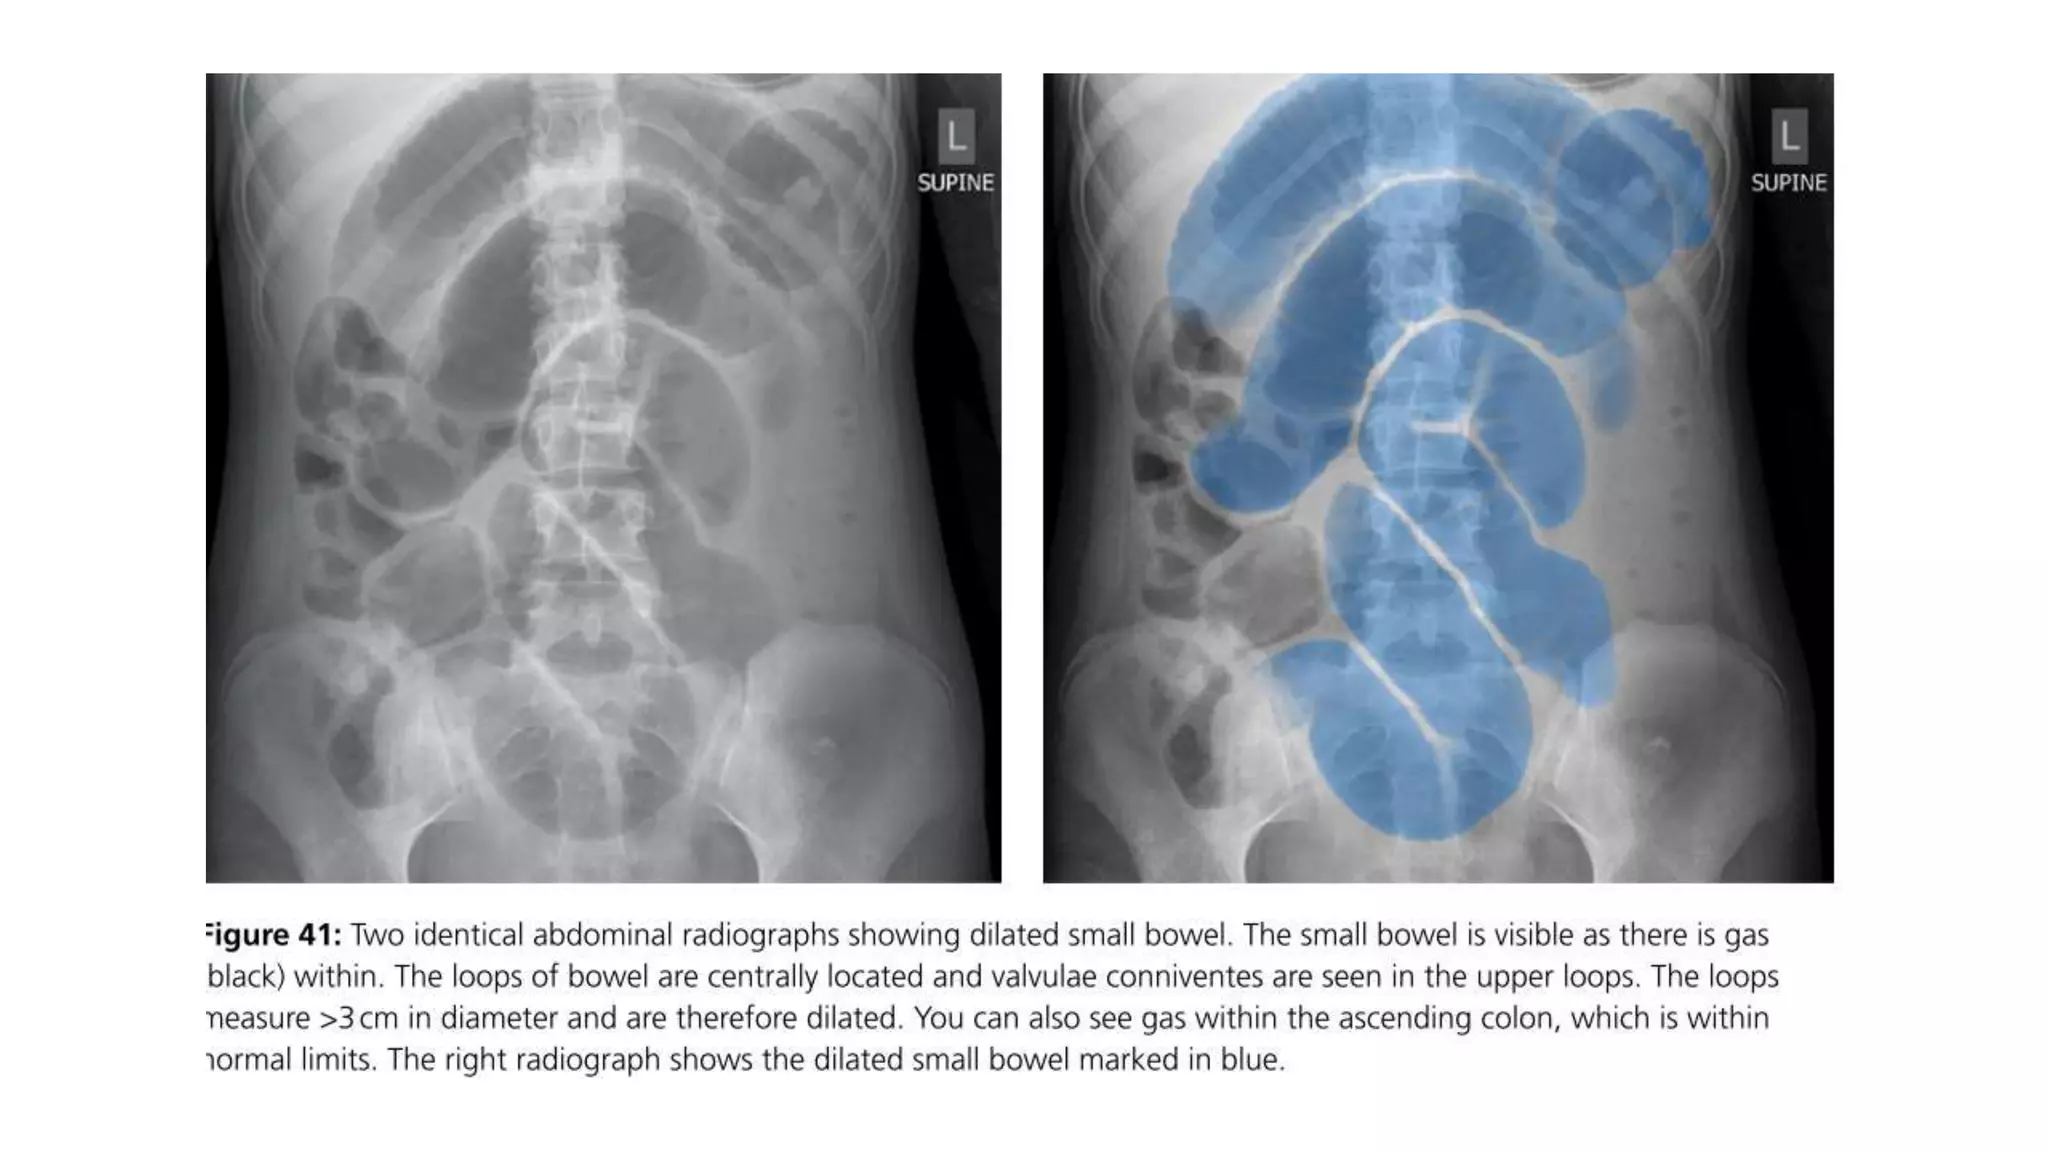

• Dilation >3 cm: The small bowel is dilated if it measures over 3 cm in

diameter.

• Central location: The dilated loops are more likely to be centrally

located on the abdominal radiograph.

• Valvulae conniventes: These are the mucosal folds of the small

intestine. They are thin, closely spaced and classically seen as a

continuous thin line across the entire width of the bowel.

• Air fluid level in upright position

• #41 Note: The height of an adult vertebral body is approximately 4 cm. You can use this as a quick comparison to estimate the diameter of the bowel. Note: Large bowel tends to be peripherally located.